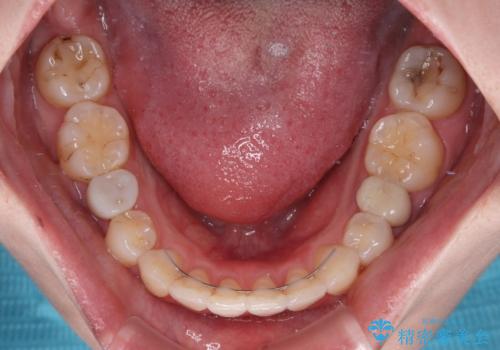

開咬と前方に飛び出した前歯 インビザラインによる矯正治療

舌の突出癖改善のトレーニングをしっかりと行っていただき、上下前歯が接触する咬み合わせを達成することができました。

- 1年5ヶ月